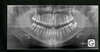

Tout d'abord, le praticien va procéder à un examen du patient (examen clinique) afin d’établir un diagnostic à la fois esthétique et fonctionnel. Des examens complémentaires tels que moulage des dents, photographies intra-buccales et faciales seront effectuées au cabinet. Des documents radiologiques complémentaires ( le plus souvent une radiographie panoramique et deux téléradiographies du crâne de face et de profil sont nécessaires pour étudier la position des dents et l'équilibre du squelette crânio-facial. L’état des dents et des gencives sera regardé avec attention.

Tous ces éléments : examen du patient, moulages, photographies, radiographies..., constituent ce que l'on appelle le dossier orthodontique.